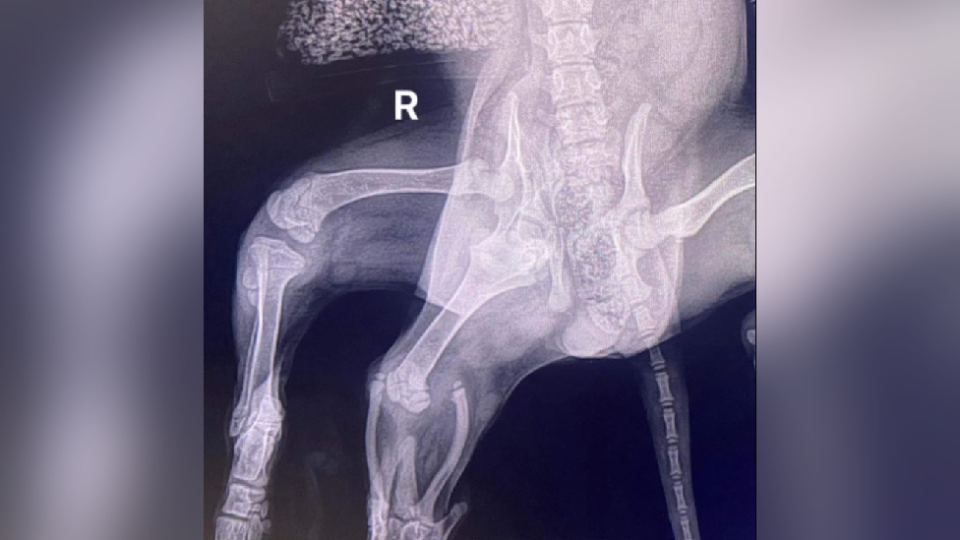

Donations for the operation totaling 15 thousand pounds for Ariel were collected literally from the whole world. The situation was complicated by the fact that the cocker spaniel had two hip joints on one side, which did not allow the pelvis to form correctly. Tomography also showed the presence of only one kidney.

X-ray showed that Ariel had two hip joints on the right side